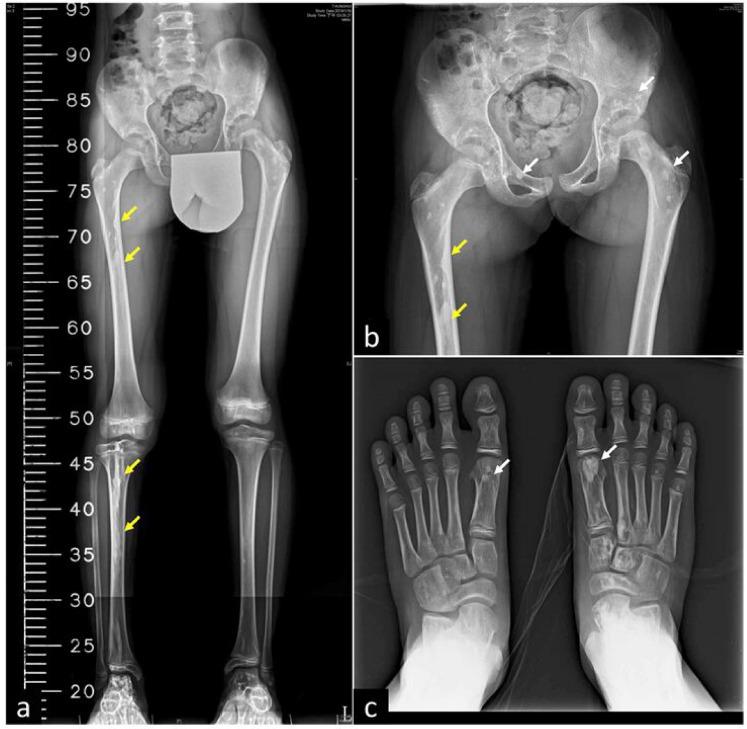

Buschke-Ollendorff syndrome (BOS) is a rare, usually benign, autosomal dominant genetic disease affecting about 0.005% globally. BOS commonly manifests with asymptomatic connective tissue nevi, sometimes with sclerotic bone lesions like osteopoikilosis or melorheostosis. However, BOS may develop severe, symptomatic complications that require surgical intervention. Here we report a 9-year-8-month girl presenting with multiple nonpruritic, nonpainful skin plaques scattered around the trunk, buttocks, and bilateral legs. She had a history of right varus foot with inadequate plantar flexion. Upon visiting, obvious leg length discrepancy (LLD) was noted. Lesional biopsy revealed increased fibroblasts within dermal collagen bundles. Verhoeff-van Gieson stain revealed scattered foci of thickened elastic fibers between collagen fibers, especially in the mid-dermis. Radiographic examination of the lower extremities showed multiple small, round-to-oval shaped, radiopaque spots on the pelvic bones, femurs, tibiae, and both feet. Hyperostosis along the long axis with "dripping candle wax" appearance was characteristic of osteopoikilosis and melorheostosis. Genetic analysis showed heterozygous point mutation in exon 1 of LEMD3 gene (c.1323C>A, p.Y441X), confirming diagnosis of BOS. Sequential and epiphyseodesis were performed to correct LLD with a favorable outcome at 2-year follow-up. BOS associated with severe bone abnormalities is rare, but orthopedic surgical intervention can provide satisfactory outcome.

布希科-奥尔伦多夫综合征(BOS)是一种罕见的、通常良性的常染色体显性遗传疾病,全球发病率约为 0.005%。BOS 常表现为无症状的结缔组织痣,有时伴有硬化性骨病变,如骨斑点症或硬化性骨髓炎。然而,BOS 可能会发展出严重的、有症状的并发症,需要手术干预。我们在此报告一例 9 岁 8 个月的女孩,其躯干、臀部和双侧腿部散在多发性无瘙痒、无痛性皮肤斑块。她曾有右侧足内翻伴足底屈肌功能不足的病史。就诊时,明显存在下肢不等长。皮损活检显示真皮胶原束内纤维母细胞增多。Verhoeff-van Gieson 染色显示胶原纤维间有散在的增粗弹性纤维灶,尤以中真皮层为著。下肢的影像学检查显示骨盆、股骨、胫骨和双脚上有多个小的、圆形至椭圆形的不透射线斑点。沿长轴的骨质增生呈“蜡烛滴蜡”样外观,具有骨斑点症和硬化性骨髓炎的特征。基因分析显示 LEMD3 基因外显子 1 存在杂合点突变(c.1323C>A,p.Y441X),确诊为 BOS。行序贯和骺融合术矫正下肢不等长,2 年随访时取得了良好的结果。BOS 合并严重的骨骼异常较为罕见,但矫形外科手术干预可获得满意的结果。